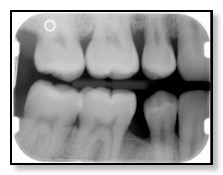

Example xray image taken during annual exam cleaning and xrays

So why do we take x-rays every year? To see in-between your teeth and inside your tooth and roots. While we’re cleaning your teeth and performing the oral exam, we can only see what is happening on the outside of your teeth.

We use our high-resolution digital x-rays to look in between and inside your teeth. We’re looking for cavities, abscesses, and any other unusual or potentially harmful issues, many of which can lead to more severe dental needs such as crowns, bridges, and root canals. We believe it is best to stay ahead of the problems, saving you money, and from pain and discomfort.